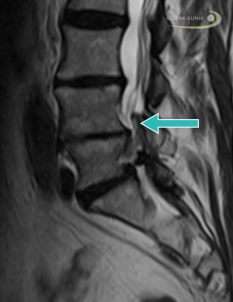

- Spinalkanalstenose: Einengung des Spinalkanals durch Knochenanbauten und Druck auf Nervenwurzeln, die zu Rückenschmerzen führen und zu Beinschmerzen, die beim Gehen stärker werden.

Wenn Spondylophyten oder Retrospondylophyten mit Blutgefäßen, Nerven oder dem Rückenmark in Kontakt kommen, drohen Schmerzen und Nervenstörungen, wie z. B. Radikulopathien. Engen die Knochenanbauten den Spinalkanal ein, entwickelt sich eine Spinalkanalstenose.